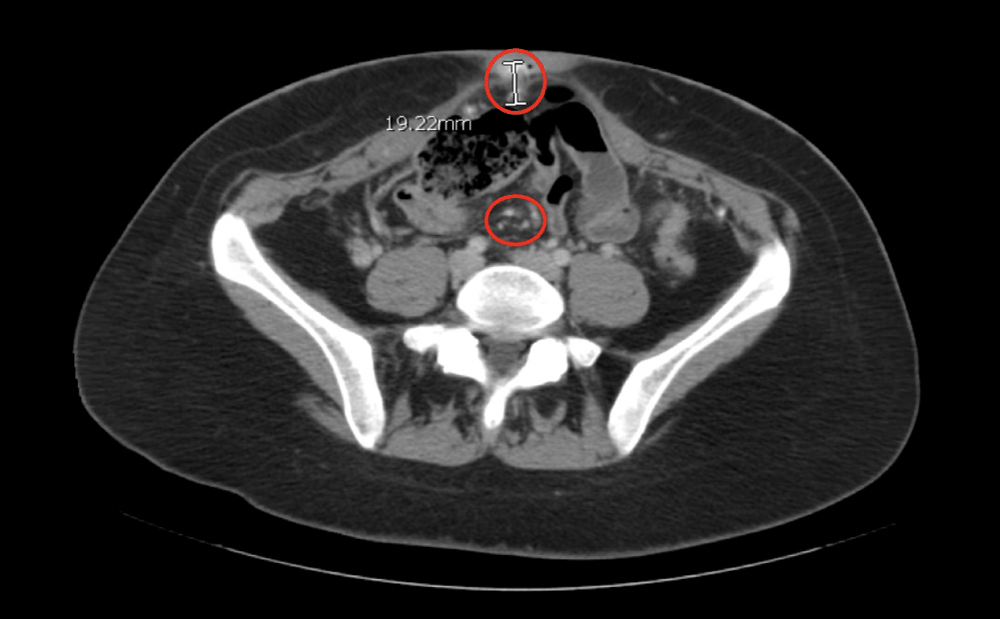

The patient is a 25-year-old white primigravid female at 41.1 weeks gestation. The pregnancy was complicated by failure of 1 hour glucose tolerance test (GTT) with refusal of 3-hour GTT. Ultrasonography at 35 and 6/7 weeks indicated the fetus was large for gestational age (LGA) but did not otherwise indicate any abnormalities, including the presence of abnormal uterine, adnexal, or pelvic organ abnormalities. She presented to labor and delivery from a birthing center for prolonged labor and prolonged rupture of membranes. Despite Pitocin augmentation, uterine contractions were inadequate and transition to cesarean delivery was recommended for failure to progress. A healthy male infant was delivered via C-section. Uterine atony was noted. Quantitative blood loss was 1326 mL, conferring a diagnosis of postpartum hemorrhage. This was managed successfully with intraoperative methergine administration. Abnormal intraoperative findings included uterine, bladder, abdominal wall, and omental nodules. A uterine nodule biopsy was obtained intraoperatively and sent to pathology, where it was initially identified as a low-grade serous neoplasm. The tumor immunohistochemistry is shown in table 1. The patient and her baby progressed through the acute postpartum period without further sequelae and were discharged home on postpartum day 2. On postpartum day 18, the patient underwent a computed tomography (CT) scan which revealed multiple partially calcified masses seen primarily in the parametrial fat which were suggestive of peritoneal based disease. Imaging studies are shown in figures 1a-1c. The patient’s care was transferred to a gynecologic oncologist, where she completed six cycles of Lupron Depot and anastrozole chemotherapy in addition to an omentectomy and a total abdominal hysterectomy with bilateral salpingo-oopherectomy. At the time of this case report, the patient is receiving combination therapy which includes traditional chemotherapy and “integrated holistic therapy” coordinated by an independent clinic in California. The information described in this case summary was collected via direct involvement in the case and thorough chart review.

Figure 1b: Computed Tomography demonstrating small partially calcified peritoneal masses and a 1.9 cm partially calcified mass in the region of the umbilicus. View Figure 1b